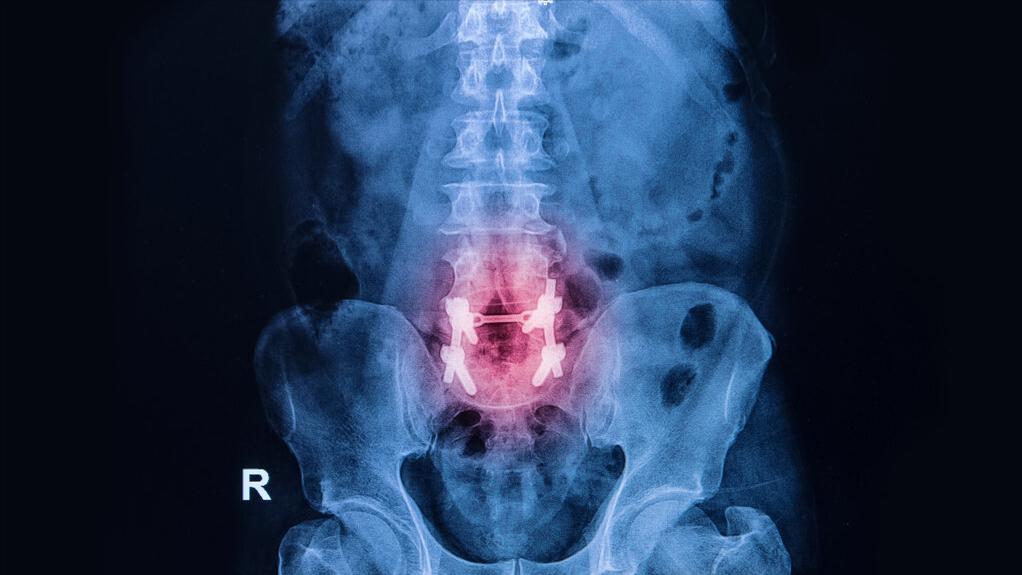

目前我国有关腰椎的手术已经相当成熟,一些手术技术也处于世界一流的水准。

脊柱外科发展到现在,已经相对精细完整,其手术技术也大多是高精尖的技术操作。在过去的一段时间,椎间盘相关疾病的手术还相对单一,仅能做到单纯的髓核摘除,无法重建椎间隙的高度。而且开窗也比较复杂,创面也较大。

而且目前的手术,很多都是微创手术,手术切面很小,而且风险也更低,效果也比以前要好得多。因此手术可以做,也并不存在做完人就瘫了的情况。